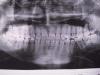

chinga Опубликовано 24 марта, 2011 Поделиться Опубликовано 24 марта, 2011 Недавно откололся кусок семерки на нижней челюсти, с правой стороны. Ходил в 3 разные стоматологии, везде предлагают разное: 1. в первой посоветовали вырвать 7ку, и что зуб мудрости займет его место. Но когда пришел к хирургу, вырывать отказался, сказал что зуб очень хороший, лучше пролечить.2. посоветовали удалить 7ку, но т.к. штатного ортодонта у них нет, отправили в другую клинику для консультации.3. там мне посоветовали лечить 7ку, а удалять зубы мудрости. Теперь вот не знаю что же делать: удалю 7ку - а вдруг его можно лечить, все таки говорят же: зубы надо сохранять до последнего.А если удалю зуб мудрости, вдруг 7ка все таки покрошится, и тогда я останусь без обоих зубов. Прилагаю панорамный снимок челюсти (тогда еще зуб не откололся, но пульпит на нем видно). Зуб мудрости справа на верхней челюсти удалял 2 года назад. Все зубы мудрости не в дуге, на нижней челюсти изза нехватки места, зубы стали вытеснять друг друга, так что с левой стороны зуб мудрости придется удалить. Что бы Вы сделали на моем месте? Спасибо. Ссылка на комментарий